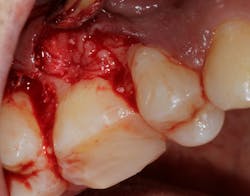

Saving compromised multirooted teeth with root amputation can often be successful, but the technique is sensitive and complex. Proper case selection is essential, and considerations include the following:

There is sufficient bone support around the remaining roots (at least 50% or more is needed) along with sufficient coronal tooth structure (figure 3).How does root amputation compare with other surgical procedures?

The prognosis is good for molar teeth treated with root amputation, provided case selection and treatment are performed properly. Fugazzottoreported 15-year cumulative success rates comparing molar root resection to molar implant placement, with survival rates of 96.8% for root-resected molars and 97.0% for molar implants.10 This study was done in private practice with proper oversight and case selection.Conclusion